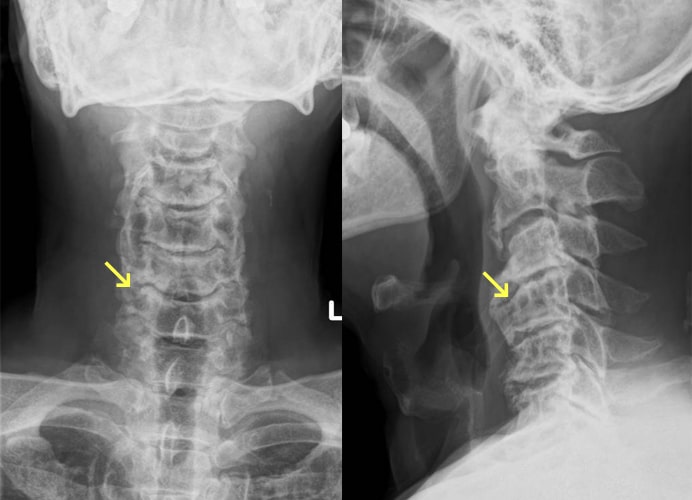

頚椎症

椎間板が年齢とともに変性し、椎間板腔の狭小化、椎体辺縁の骨硬化・骨棘形成、椎間関節の狭小化などの所見が認められるようになります。好発高位は中下位頚椎ですが、高齢者では下位頚椎が可動域を失うことで上位の椎間にストレスが集中するため、C3・4椎間に病変を認めることも多いです。頚椎症により椎間孔および脊柱管が狭窄し神経症状を引き起こします。主な症状は頚椎症そのものによる頚肩部の疼痛、運動制限のほか、神経根や脊髄が圧迫されると痺れや痛み、麻痺などの神経症状が出現します。まずは頚椎の安静を目的に頚椎カラーを使用したり、疼痛に対しては、消炎鎮痛剤の服用、温熱療法や理学療法などが行われます。